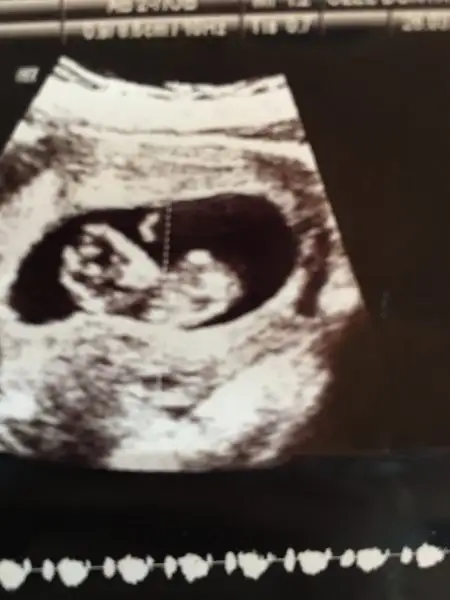

Uyuyodur cnm benkmkıde bıara uyuyodu gordm korktm hatta yaramazlarGünaydın kızlar. İkili teste geldim. Ense kalınlığına bakamadi dr. Cunku bebis kımıldamıyor. Kalp atisi var da şükür. Bir seyler ye ic bakalim dedi. Bakti yine tık yok. Yarim saate tekrar bakalimdedi. Birazdn giricem tekrar

Günaydın kızlar. İkili teste geldim. Ense kalınlığına bakamadi dr. Cunku bebis kımıldamıyor. Kalp atisi var da şükür. Bir seyler ye ic bakalim dedi. Bakti yine tık yok. Yarim saate tekrar bakalimdedi. Birazdn giricem tekrar